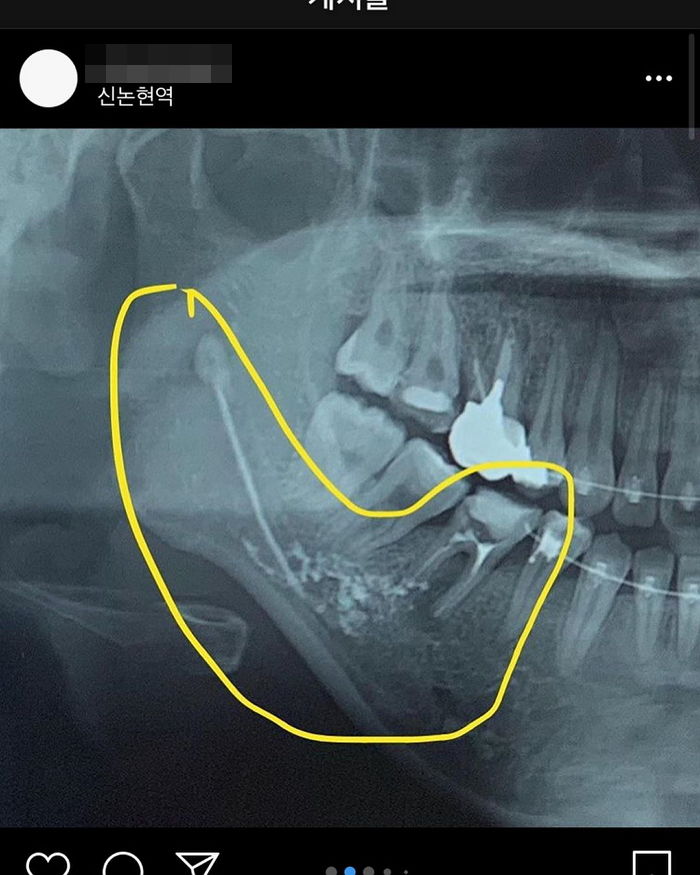

해당 게시글에는 신경 치료를 받던 중 의료 사고가 일어났다는 내용과 함께 아랫니 엑스레이 사진이 게재됐다.

사연에 따르면 A씨는 신경 치료 중 약물이 신경관으로 넘어가 하치조 신경이 마비됐다. 하치조 신경이란 아래턱 신경에서 턱뼈관으로 이어져 아래 치아와 아래턱뼈에 분포하는 신경이다.